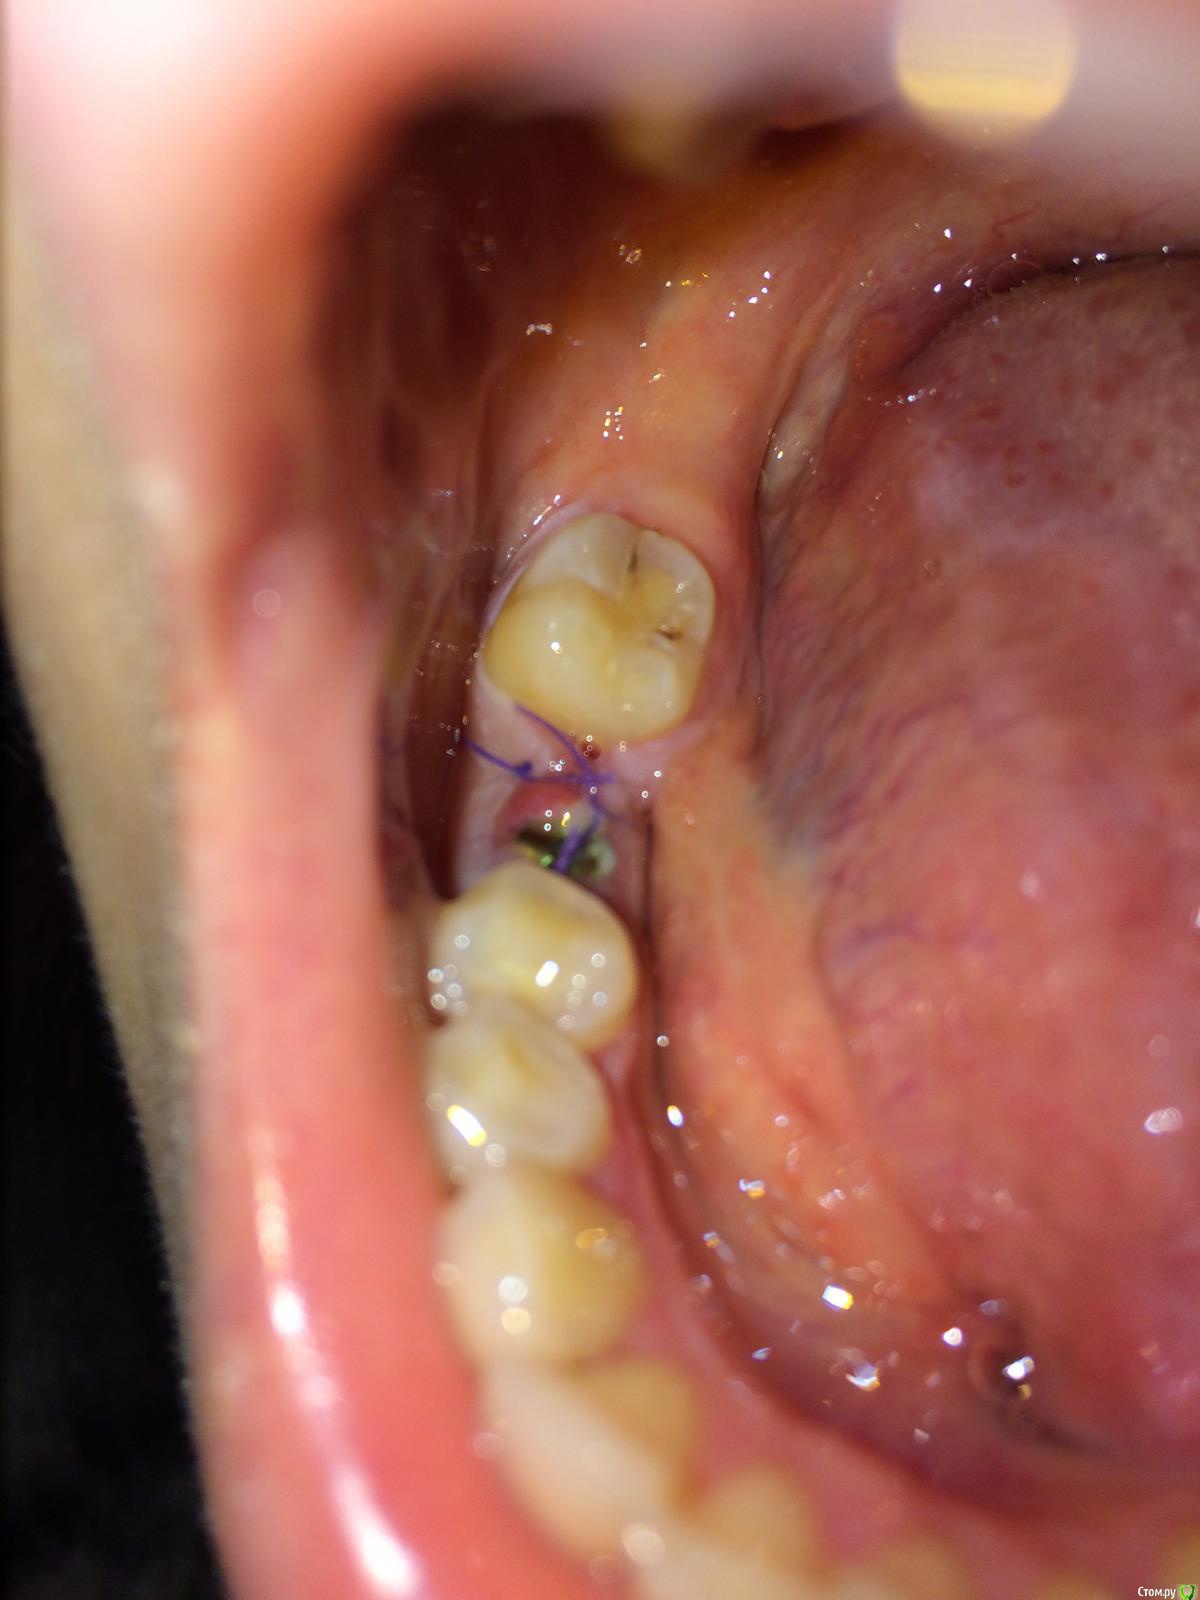

flyfli Опубликовано 20 октября, 2017 Поделиться Опубликовано 20 октября, 2017 (изменено) Уважаемые доктора,помогите ,пожалуйста, очень переживаю,сегодня 5 ый день после имплантации и возле формирователя немного красновато и припухло с одной стороны, боли нет,но очень страшно,все ли впорядке как вы думаете? Такое может быть покраснение нормой? Изменено 20 октября, 2017 пользователем flyfli Ссылка на комментарий

flyfli Опубликовано 20 октября, 2017 Автор Поделиться Опубликовано 20 октября, 2017 там формирователь, вот попробовала поближе там обвела кружком подозрительное место Ссылка на комментарий

red_butler Опубликовано 20 октября, 2017 Поделиться Опубликовано 20 октября, 2017 там формирователь, вот попробовала поближе там обвела кружком подозрительное местотогда ничего страшного, антисептическая обработка и ждать Ссылка на комментарий